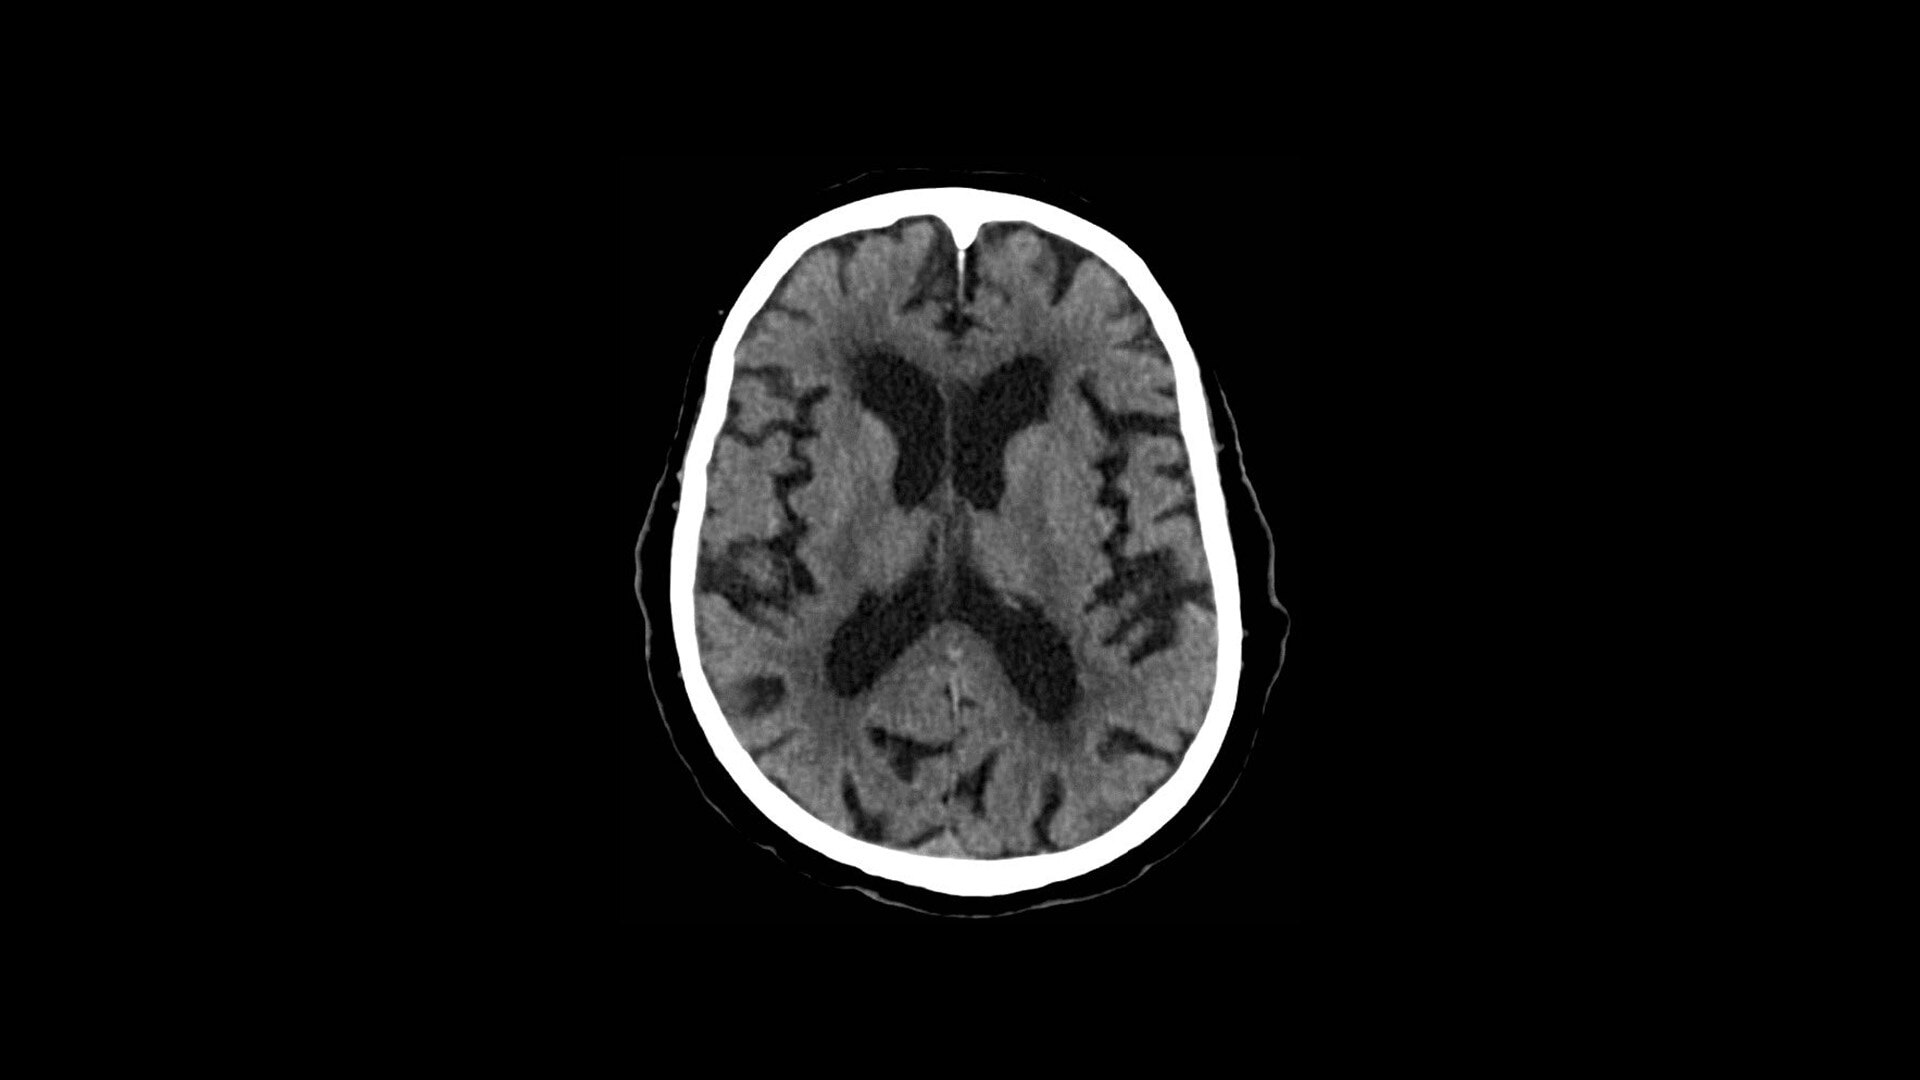

TrueFidelity DL

Deep learning for a deeper understanding

TrueFidelity™ DL is our state-of-the-art image reconstruction technology that uses a DNN to generate high-definition, low-noise CT images. It produces images with exceptional sharpness, low-contrast image quality performance and your preferred noise texture, at the same dose.¹